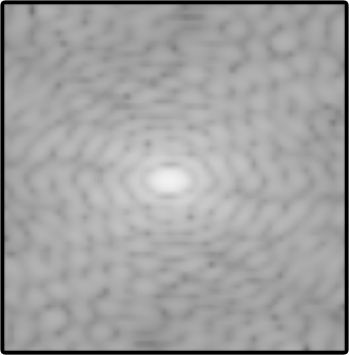

Objectives: Present a novel deep learning-based skull stripping algorithm for magnetic resonance imaging (MRI) that works directly in the information rich k-space. Materials and Methods: Using two datasets from different institutions with a total of 36,900 MRI slices, we trained a deep learning-based model to work directly with the complex raw k-space data. Skull stripping performed by HD-BET (Brain Extraction Tool) in the image domain were used as the ground truth. Results: Both datasets were very similar to the ground truth (DICE scores of 92\%-98\% and Hausdorff distances of under 5.5 mm). Results on slices above the eye-region reach DICE scores of up to 99\%, while the accuracy drops in regions around the eyes and below, with partially blurred output. The output of k-strip often smoothed edges at the demarcation to the skull. Binary masks are created with an appropriate threshold. Conclusion: With this proof-of-concept study, we were able to show the feasibility of working in the k-space frequency domain, preserving phase information, with consistent results. Future research should be dedicated to discovering additional ways the k-space can be used for innovative image analysis and further workflows.